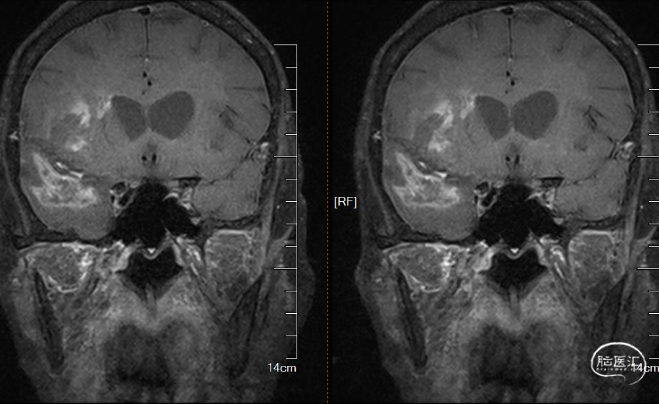

血管壁成像